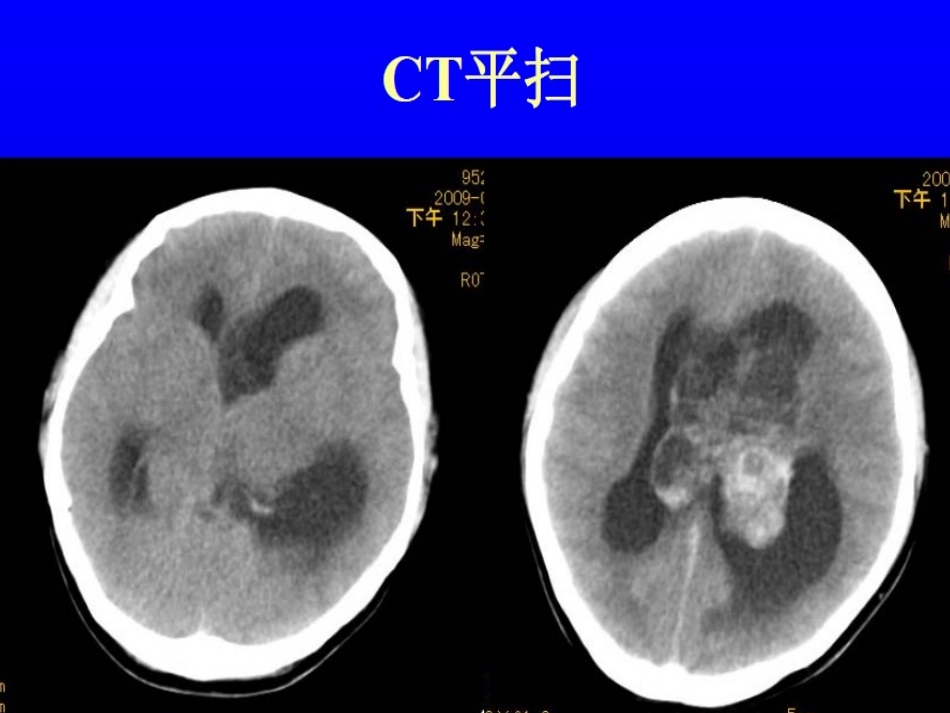

病例讨论病例讨论T1WIT1WIT2WIT2WIT1WI+CT1WI+CT1WI+CT1WI+C请讨论请讨论病理病理中枢神经细胞瘤中枢神经细胞瘤神经上皮组织肿瘤神经上皮组织肿瘤􀀩􀀩1.1.星形细胞肿瘤星形细胞肿瘤􀀩􀀩2.2.少枝胶质细胞肿瘤少枝胶质细胞肿瘤􀀩􀀩3.3.室管膜肿瘤室管膜肿瘤􀀩􀀩4.4.脉络丛肿瘤脉络丛肿瘤􀀩􀀩5.5.其它神经上皮肿瘤其它神经上皮肿瘤􀀩􀀩6.6.神经元和混合神经元神经元和混合神经元--神经胶质肿瘤神经胶质肿瘤􀀩􀀩7.7.松果体区肿瘤松果体区肿瘤􀀩􀀩8.8.胚胎性肿瘤胚胎性肿瘤临床特征好发于20-40岁(8天-67岁,平均29岁)。多数生长在幕上脑室的中线部,易阻塞Monro孔,引起梗阻性脑积水。肿瘤生长较慢,由于病变在脑室内缓慢生长且有足够的生长空间,出现临床症状较晚,肿瘤常常体积较大。影像学表现CNC主要见于侧脑室前壁,多邻近透明隔,肿瘤巨大时可突入第三脑室或对侧侧脑室,透明隔明显向对侧移位。关于关于CNCCNC的诸家观点的诸家观点􀀩􀀩胡凌,高培毅胡凌,高培毅.2003.2003凡青年人位于透明隔的肿瘤,应考虑中枢性神经细胞瘤凡青年人位于透明隔的肿瘤,应考虑中枢性神经细胞瘤的诊断。的诊断。􀀩􀀩赵天平,程敬亮,张勇,等赵天平,程敬亮,张勇,等.2009.2009当肿瘤体积大,侵及胼胝体、侧脑室顶壁及侧壁,出当肿瘤体积大,侵及胼胝体、侧脑室顶壁及侧壁,出现胼胝体下方和侧脑室顶呈网状或丝条状垂向下的瘤体组织现胼胝体下方和侧脑室顶呈网状或丝条状垂向下的瘤体组织征象及条索状牵拉侧脑室侧壁的征象时,应首先考虑征象及条索状牵拉侧脑室侧壁的征象时,应首先考虑CNCCNC的可能。的可能。诊断依据诊断依据1)1)青壮年青壮年2)2)以室间孔、透明隔为中心。范围大,累及一侧脑室、以室间孔、透明隔为中心。范围大,累及一侧脑室、双侧脑室,或同时累及第三脑室。病变的成份多样双侧脑室,或同时累及第三脑室。病变的成份多样化,囊变、坏死、出血、钙化。化,囊变、坏死、出血、钙化。3)CT3)CT:中等密度,较高密度、较低密度和钙化。:中等密度,较高密度、较低密度和钙化。4)MRI4)MRI::T1WIT1WI中等信号与低信号影,中等信号与低信号影,T2WIT2WI高高和较高信号及较低信号。增强后,实质性部分中度和较高信号及较低信号。增强后,实质性部分中度至明显的强化,囊变区无强化,囊实相间的比例多至明显的强化,囊变区无强化,囊实相间的比例多样。样。参考“泡状”和“条索状”征参考“泡状”和“条索状”征象。象。““泡状泡状””和和““条索状条索状””征征象象